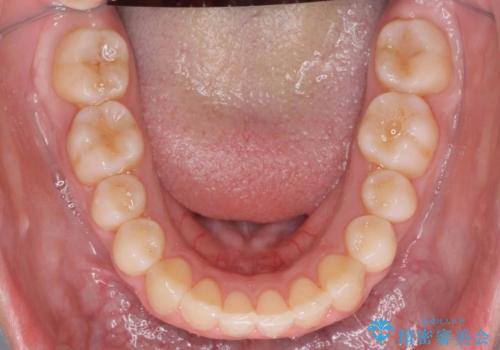

- 出っ歯を主訴に来院。

上の歯を全体に大きく後ろに下げる治療計画を立てました。

後ろに下げるために、親知らずは抜歯しています。

後ろに下げるために、ワイヤー矯正の前にカリエールという装置を使用しました。